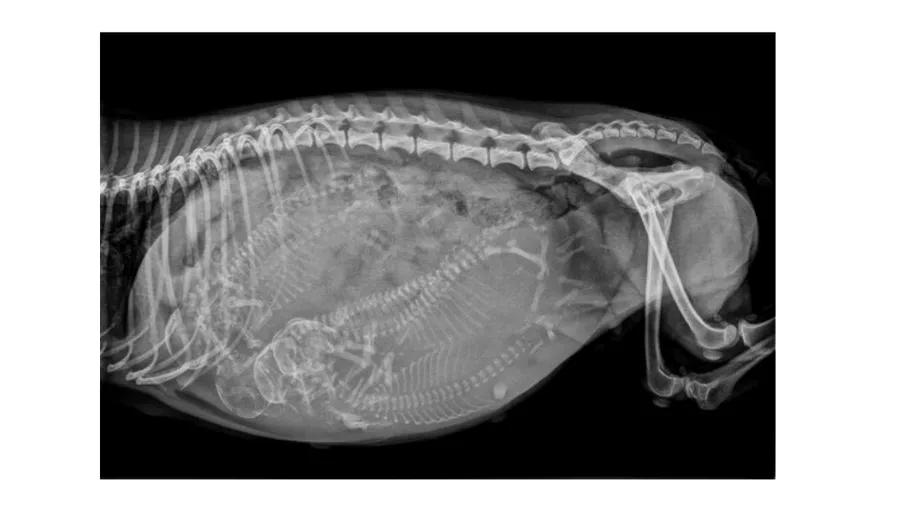

Which diagnostic method can first reliably confirm pregnancy in the bitch by detecting mineralisation of the foetal skeleton?

Abdominal palpation at 28 days

Ultrasound at 16 days

Radiography at 30 days

Radiography at 45 days